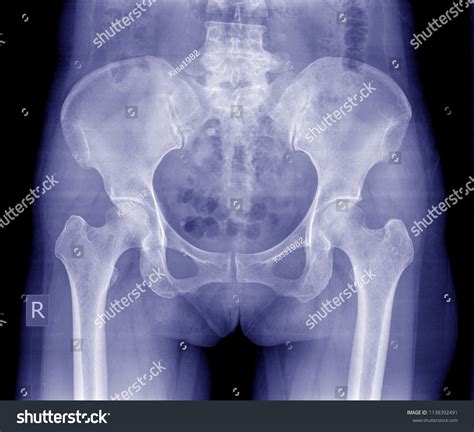

What is a Normal Hip X Ray?

A Normal Hip X Ray is a radiographic image used to visualize the hip joint and surrounding structures. It helps in diagnosing a wide range of conditions, including fractures, dislocations, arthritis, and developmental abnormalities. The term โ€œnormalโ€ refers to the expected appearance of the hip joint in the absence of any pathological conditions.

Interpreting a Normal Hip X Ray requires a trained eye. Radiologists look for specific features to determine the health of the hip joint. Key elements include:

• Bone Density: The density and structure of the bones should appear uniform and without any fractures or lesions.

• Joint Space: The space between the femoral head and the acetabulum should be consistent and without narrowing, which could indicate arthritis.

• Alignment: The femoral head should be properly seated within the acetabulum, and the neck of the femur should align correctly with the shaft.

• Soft Tissues: The surrounding soft tissues should appear normal, without any swelling or abnormalities.